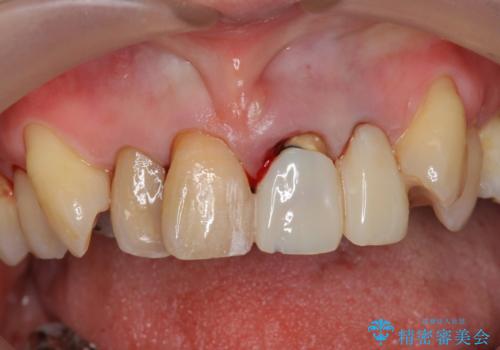

前歯の見た目をオールセラミッククラウンで改善

- 前歯のぐらつき、見た目の改善を希望され来院されました。

ぐらつきのある歯は、破折が認められ、その他前歯も不十分な根管治療や不適合なクラウン、レジン修復により審美障害が起きています。

オールセラミックによる審美的な仕上がりに満足いただくことができました。